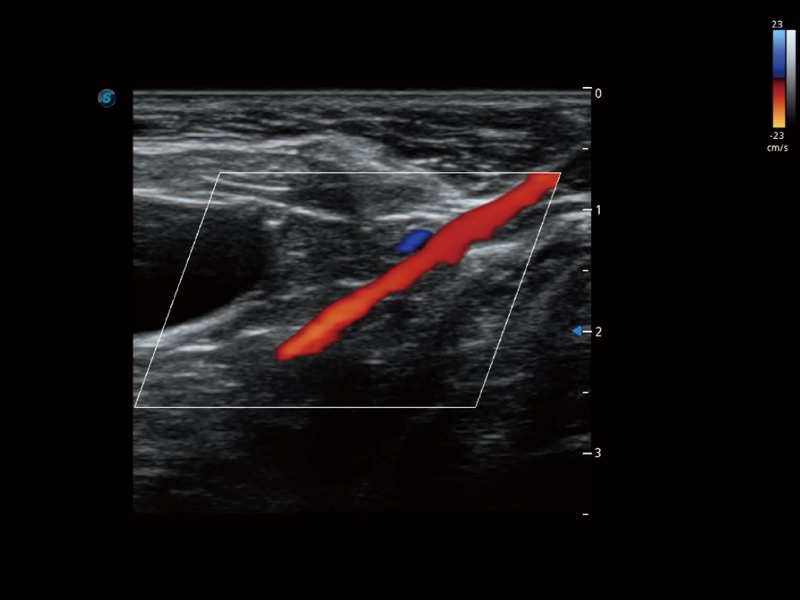

通过色彩血流和实时宽景相结合,可观察到完整的静脉或动脉的血流,方便医生检查。实时扫查过程中,如有任何操作失误也可以很容易地进行回扫擦除,而不会中断扫查。

为精细结构及组织边缘提供高清晰度的图像和更大的成像视野。帮助减轻医生的用眼疲劳,快速精准获得测量的数据。